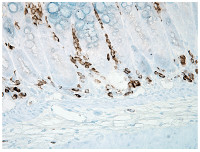

Application example

IHC using anti-Nitrotyrosine mouse monoclonal antibodies, Clone 39B6. Tissue: inflamed colon. Species: Mouse. Fixation: Formalin. Primary Antibody: Anti-Nitrotyrosine mouse monoclonal antibody Dilution: 1:1000000 for 12 h/4°C. Secondary Antibody: goat anti-Mouse biotin conjugated at 1:2000 1 h/RT. Counterstain: Mayer Hematoxylin (purple/blue) nuclear stain at 200 µl for 2 minutes at RT. Magnification: 40x. - Additional Information